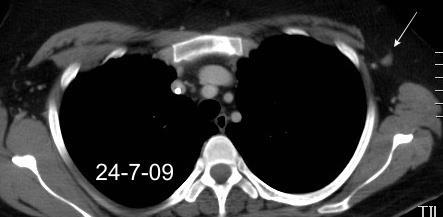

Masa axilar izquierda y derrame pleural derecho. Implantes pleurales, paraespinales . Ganglios en mamaria interna. Linfoma B difuso

2005. Masa pulmonar.

Pliegue axilar Normal

Rehúsa cirugía

2011. Acude por masa axilar

Linfoma NH de cél. B. Invasión Transtorácica.

Afectación axilar